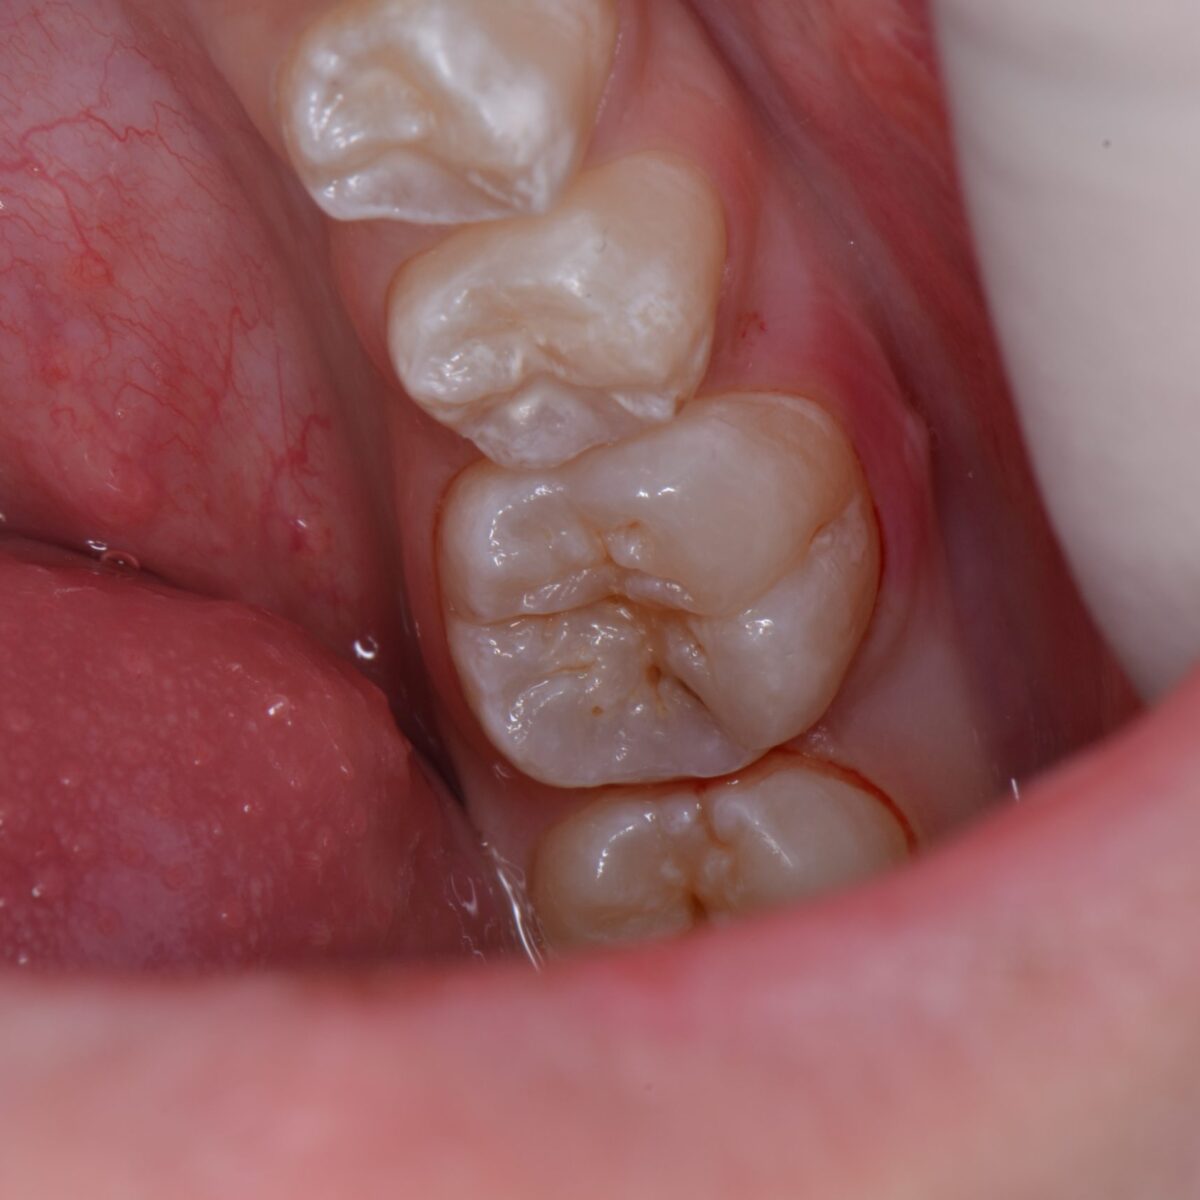

どこにあるのかわかりますか?

【東京メトロ東西線妙典駅 徒歩5分の歯医者】市川、妙典の歯科医院、めぐりデンタルクリニックの梶原です。 最近、(`・ω・´)「写真をブログや他の場面で使ってもいいですか?」٩( &…